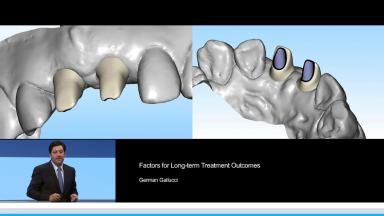

Factors for Long-term Treatment Outcomes

Long-term success in implant dentistry is based on the primary outcome of an implant-prosthetic complex taken as a whole. This presentation addresses current trends and scientific evidence on risk assessment, treatment planning, and implant prosthodontic considerations as indicators of treatment success. In particular, the most frequently used criteria to define treatment success for implant rehabilitations are updated. These include implant level, peri-implant soft tissue, prosthodontics, and patient satisfaction parameters. Additionally, the potential of digital dental technology to improve the accuracy of care delivery according to a specified treatment plan and to reduce complications is presented as a factor for ensuring long-term outcomes.